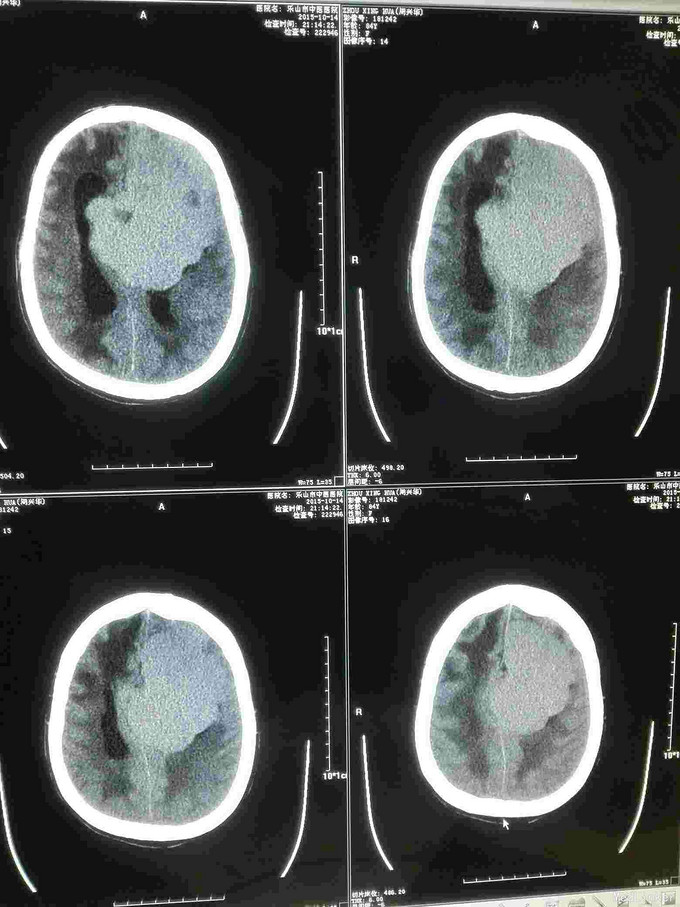

急诊CT病例

主诉 病史

昏迷不醒就诊